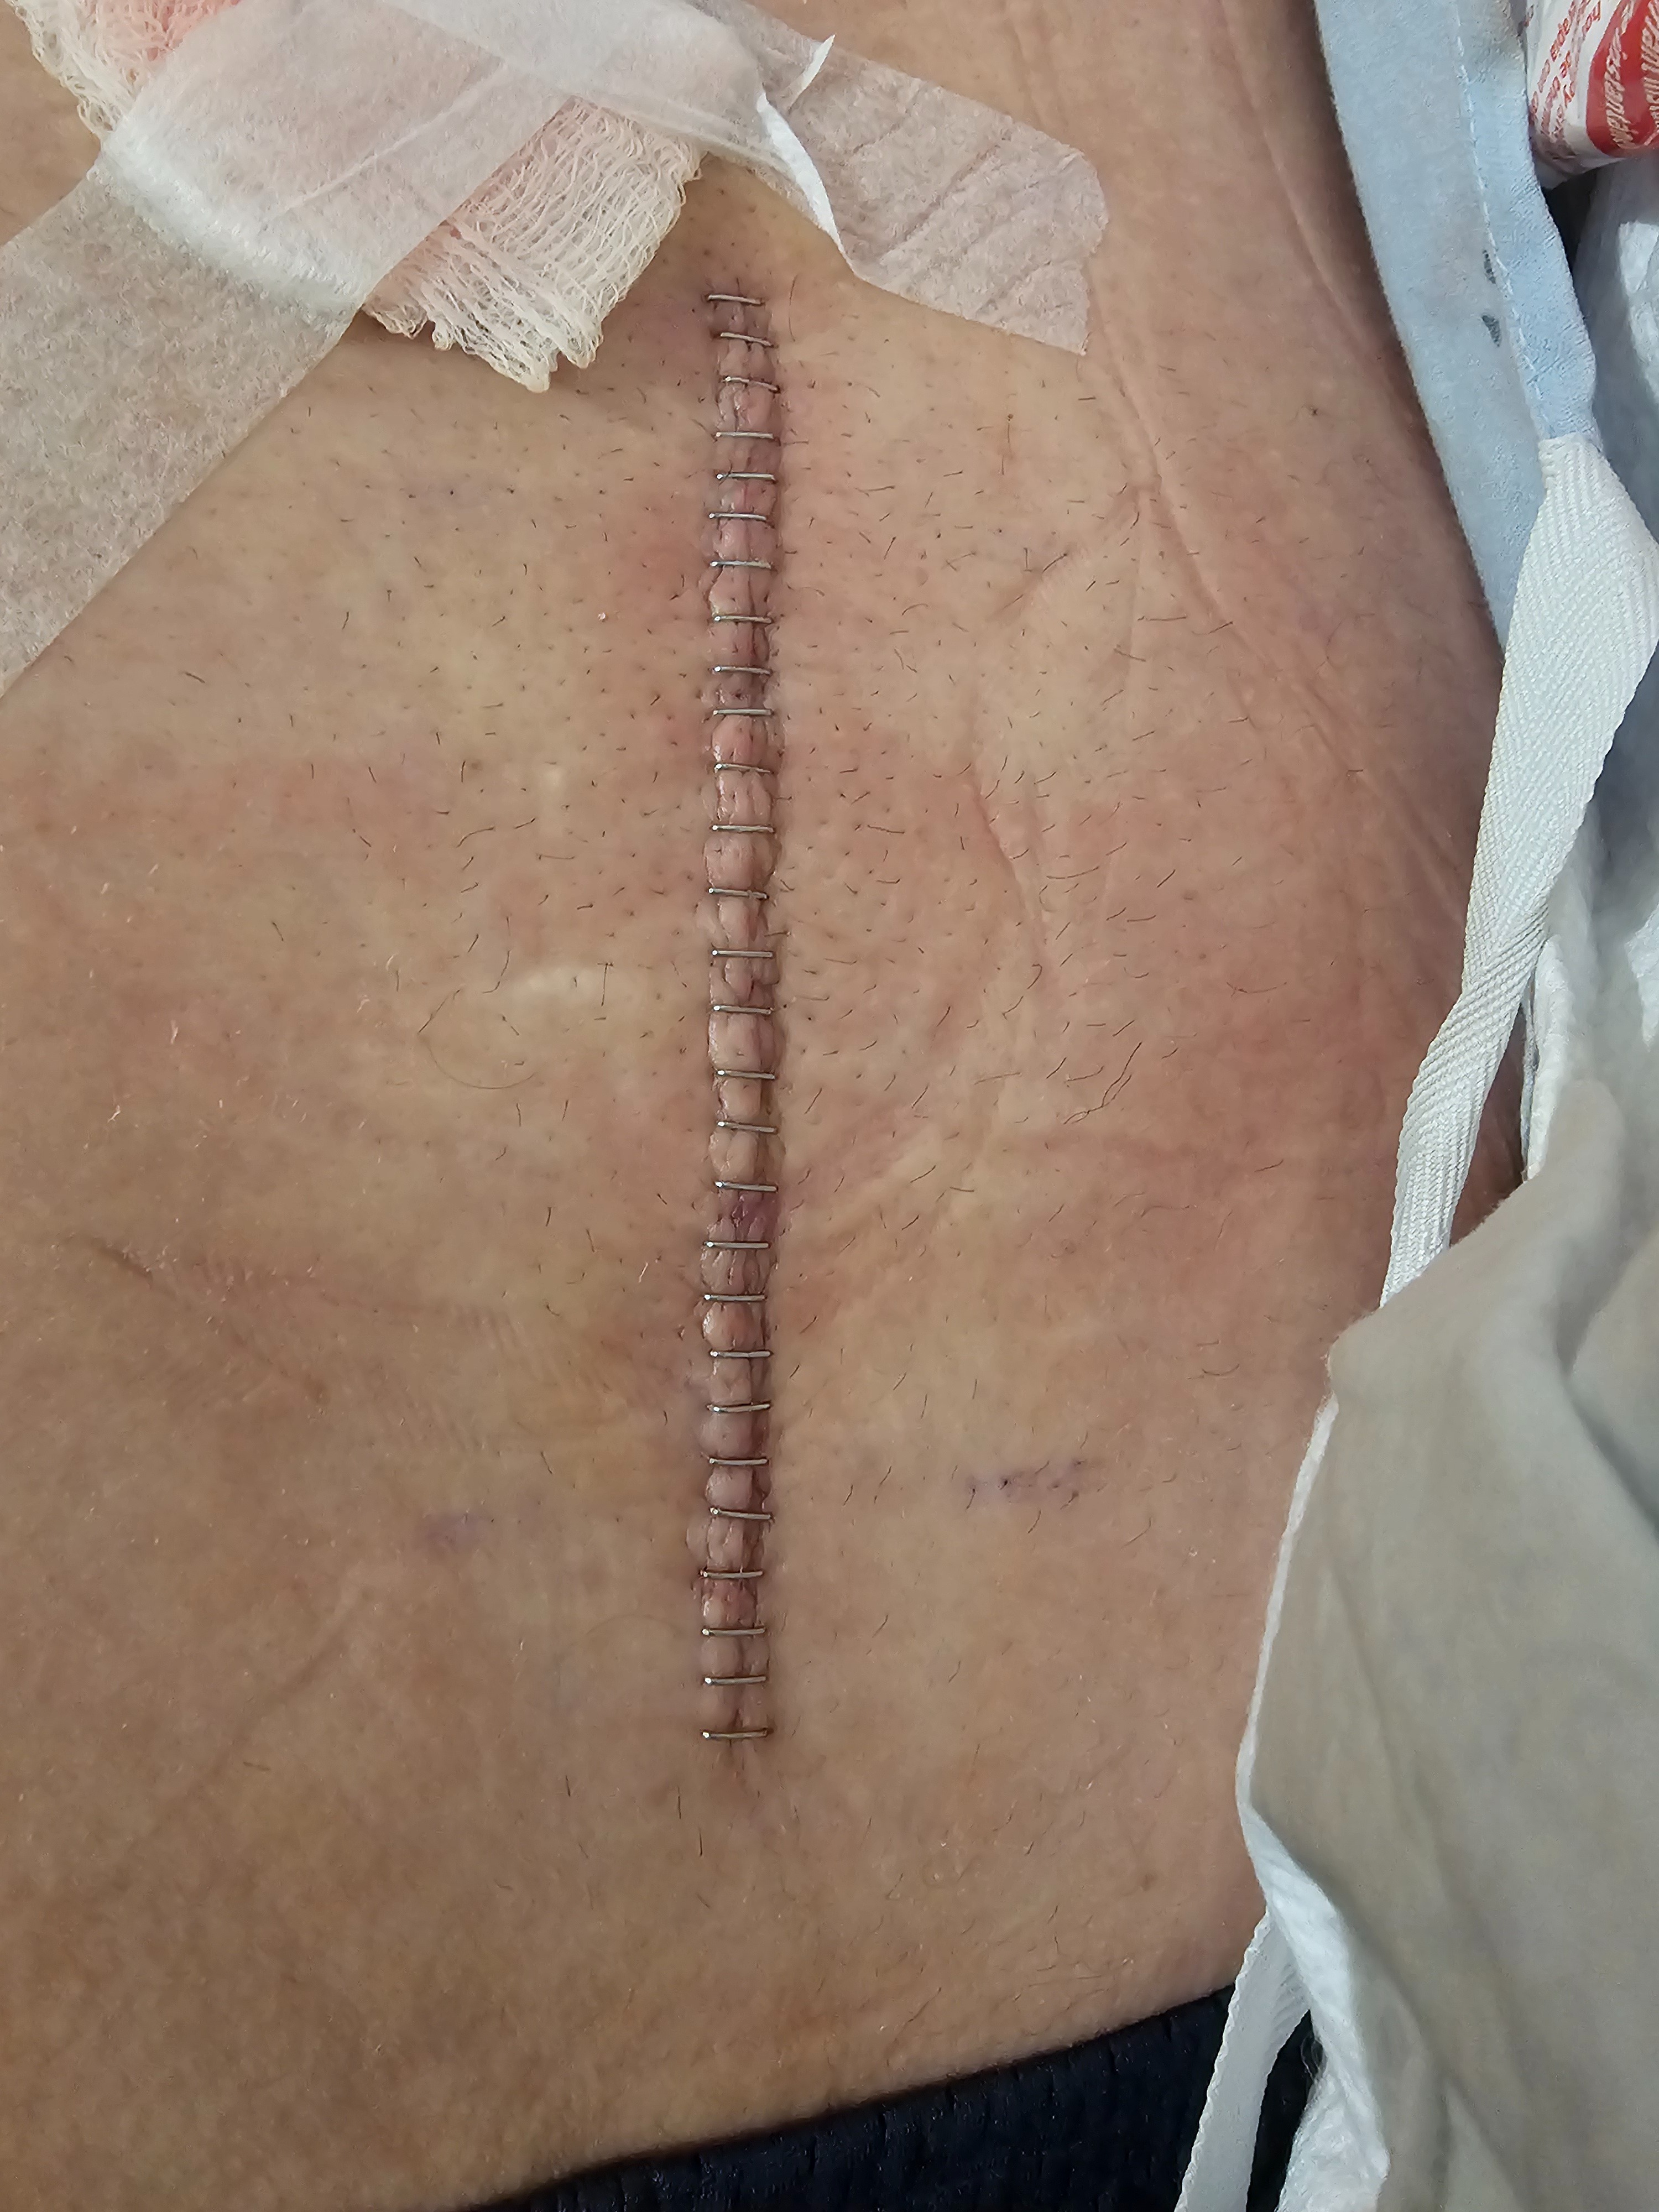

Hi, my name is Daniel Challburg and I am suffering from a incapacitating lower back injury from working in plumbing trades. I am a journeyman plumber with U.A. Local#343. I started feeling my disability in December of 2023. I reported my injury to my supervisor with an x-ray from my health provider, which is when my supervisor then instructed me to take some time off work before the Christmas holiday to try and get better. It is now October 19th, 2025 and I have not been able to return to work. I currently am trying to get Social Security Disability in California but they keep telling me that they are backed up. I have pulled a lump sum from my retirement to live off of but that money is vanishing fast every month. I need financial help! My wife works full time as a DUI Councelor but her money will not cover everything, since I've been disabled. I used to be the bread-winner and now all I can do is pray that I get better. I do physical therapy almost everyday and it usually only works when I'm using my pain medication. I went through a spinal cord stimulation trial on October 8th thru October 15th. The surgeon took the stimulation device out and now I'm experiencing severe pain levels again. I am getting a permanent spinal cord stimulation surgery in the future but am waiting for the surgeon to set the date up. Will you please help my family out financially during my difficult time. I have never asked for this type of help before and if and when I get better I would like to pay it forward for someone who needs help like I do. God bless